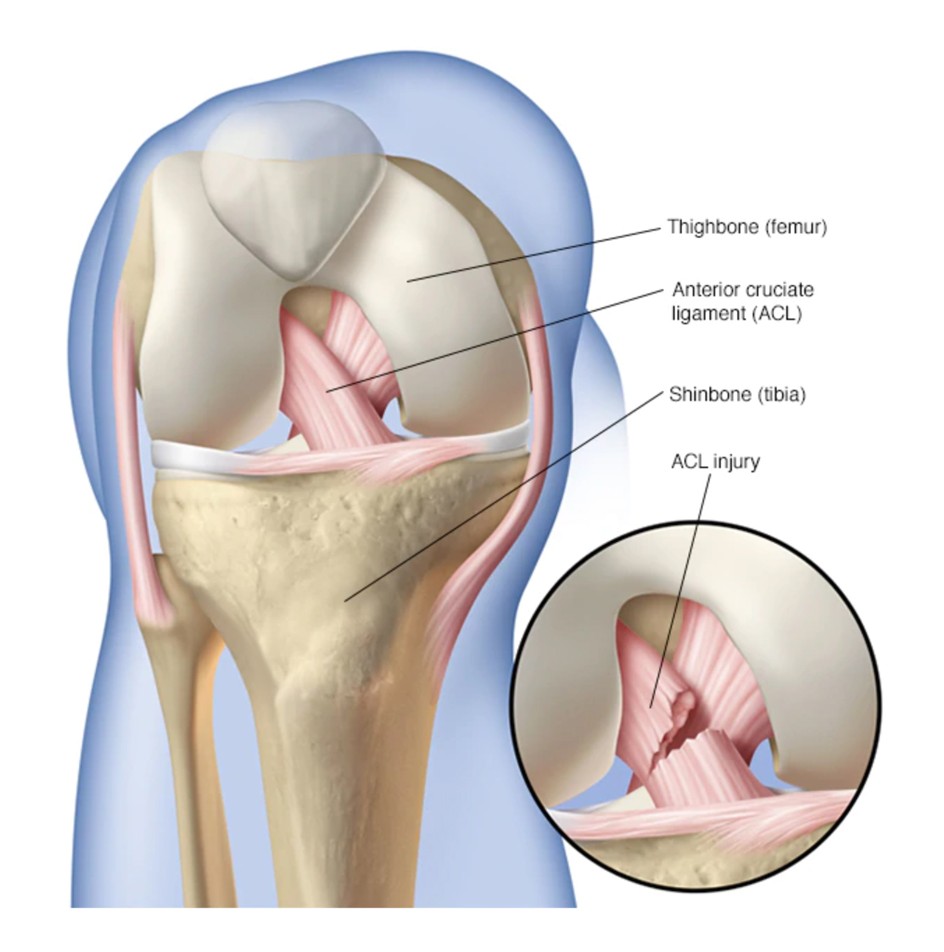

An ACL tear is a common knee injury, especially among athletes. The anterior cruciate ligament (ACL) is one of the key ligaments that helps stabilize the knee joint. A sudden twist, jump, or direct blow can cause the ligament to tear, leading to pain and instability.